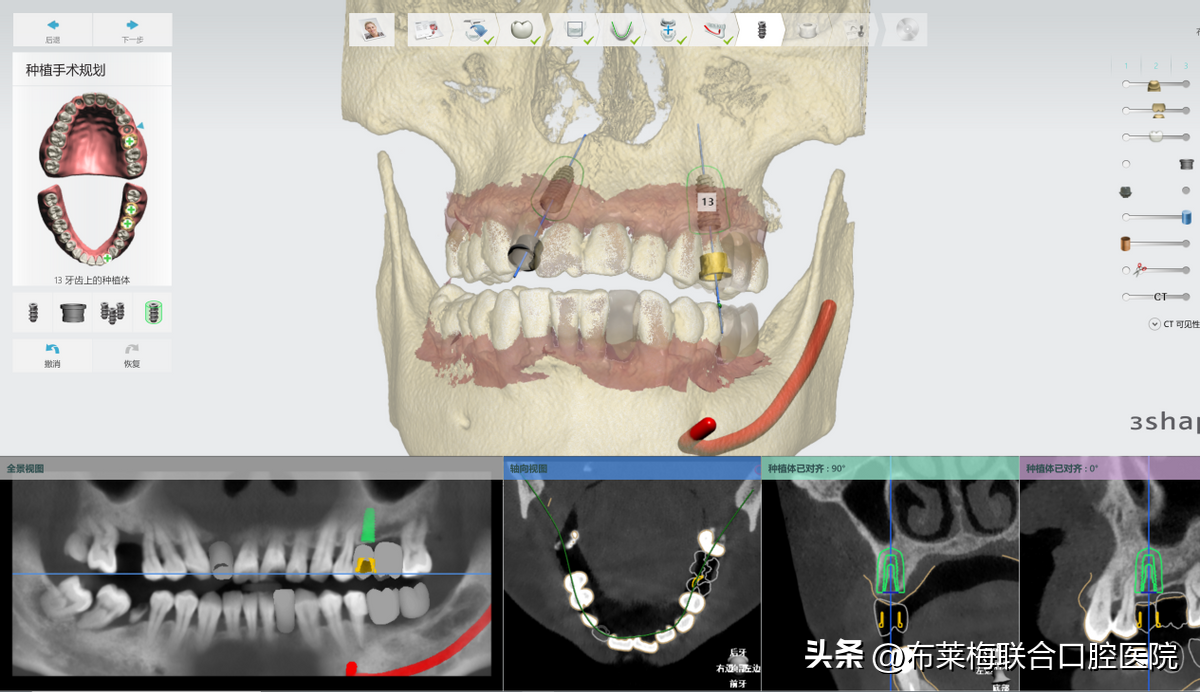

數(shù)字化種植牙技術(shù)可以讓醫(yī)生提前設(shè)計(jì)出調(diào)節(jié)方案,再在計(jì)算機(jī)上模擬生成術(shù)后果圖供患者和家屬確認(rèn)。

真真實(shí)實(shí)的在大屏幕上看到自己的方案,以及種植操作時(shí)的過程,植體走哪里安進(jìn)去,有沒有避開神經(jīng),都是一清二楚。不僅放患者安心,更讓陪同的家屬放心

數(shù)字化種植牙技術(shù)簡單來說,就是手術(shù)中提前預(yù)判好術(shù)中可能會(huì)出現(xiàn)的風(fēng)險(xiǎn),同時(shí)把誤差減少到毫米,提前讓醫(yī)生和患者知悉確認(rèn)的。降低了手術(shù)的風(fēng)險(xiǎn)系數(shù),也可以讓患者稍微放松心情??謶质窃从谖粗?,那將這些信息都提前告知患者和家屬,自然對(duì)手術(shù)也就不會(huì)過度緊張

數(shù)字化種植牙利用計(jì)算機(jī)計(jì)算出牙骨組織情況,準(zhǔn)確測(cè)量種牙的位置、角度、深度,做到量體裁衣